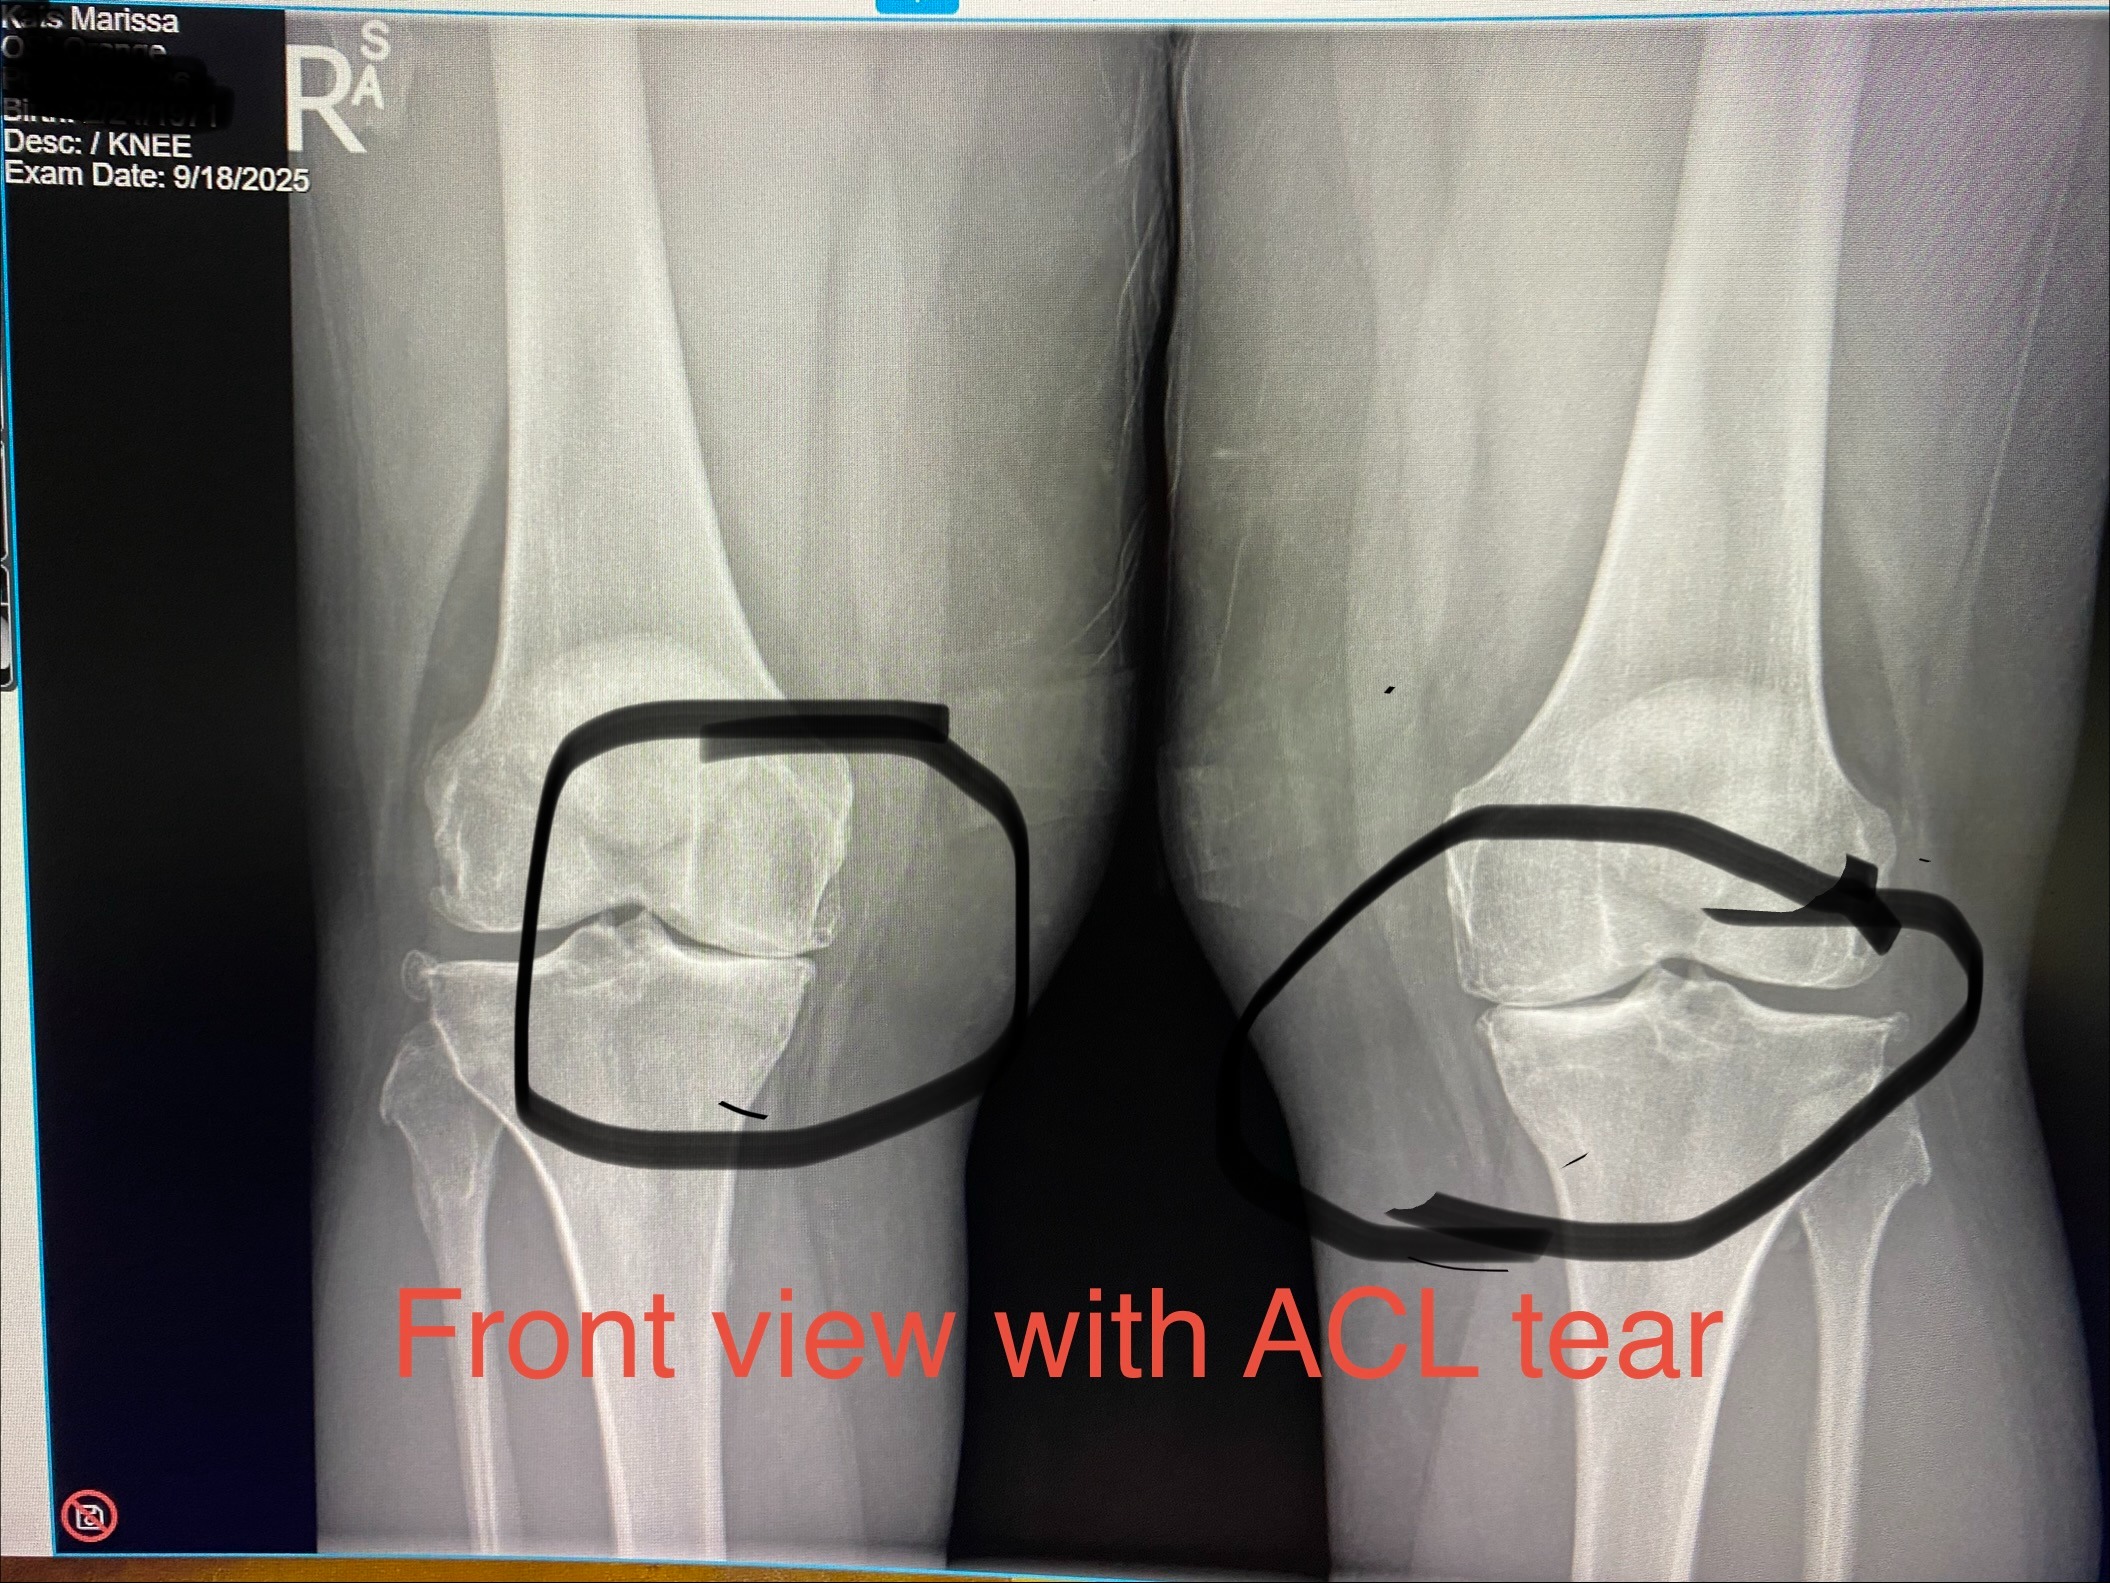

OK, all you Arlington High School people that I should’ve arrested back in the day but didn’t - LOL! Our girl needs our help! As many of you know, Marissa is like a daughter to me. If you have followed along with her posts, you know that she was severely injured at work several years ago and went through several surgeries to fix her neck and hands to be able to walk and not have numb fingers. Because she was off for so long healing and her surgeon couldn’t release her back to work, her company let her go after 23 years of hard work and employment! So, she pulled up her bootstraps and found another job in the medical field that she really loved as she felt she was helping people struggling with orthopedic care, like she was. Seven months ago, after saving the company a ton of money a month in logistics costs, they decided to lay her off due to budget cuts (basically used her) and that was the start of her spiral. She got unemployment for a few months, but that has run out months ago and wasn’t enough to live on and pay all the bills anyway, and her savings has now run out! Too young to retire, too young to pull any 401k without massive penalties which will just hurt her again later in life anyway, and she is at her wits' end trying to survive. She has done an array of different jobs in her life and is a hard, loyal, and dedicated worker. She has put over 70 applications in, but because she’s “older” and there are so many people unemployed right now, she is having a hard time even getting any jobs that she is more than qualified for to even interview her. She has many years in logistics and transportation, management (various industries), private investigation, sales, dispatching, running youth sports camps, customer service, and some administrative work. Please let me know if you know of any companies looking for a great employee. In the meantime, she’s really struggling to make ends meet and keep her sanity with all the job rejections and needs our help! She lives in a modest 1-bedroom apartment with her cat, drives a 2014 car – those of you that know her know she is not glitz and glamour. She has a little part-time gig she’s doing at night, but it’s not enough to pay the bills and it doesn’t offer any benefits or health insurance, and everything is stacking up! Because of her part-time job, she doesn’t qualify for Medi-Cal and Covered CA is going to cost her $472 a month for a regular HMO, but she has to have insurance so she needs to pay it. It is a flawed system to charge that much when you’re making very little. From all the sports and hiking and walking and jumping in and out of trucks for a living, her knees are now bone on bone, she has an ACL tear in the left one and needs both knees replaced. In the meantime, she needs to get some knee injections to manage the pain. Her parents are older and on a limited income and just aren’t able to help her in any significant way. I don’t want to see her lose her place and be living in her car with her cat! So, if you would please help me help her out, we would both be so appreciative! She was too embarrassed and has too much pride to initiate the GoFundMe herself and wanted to keep her issues on the down low, but I told her you have a lot of friends out there and you were a good friend to a lot of people, so I’m sure they would be willing to help, you just have to ask! So here we are reaching out in kind hopes that if you are able to donate, you will. I would like to raise enough to get her caught up, but also enough so she has some to lean on the next few months while she still tries to land a job. The stress of all this has taken her joy and is just dragging her down. Thank you for helping our girl!